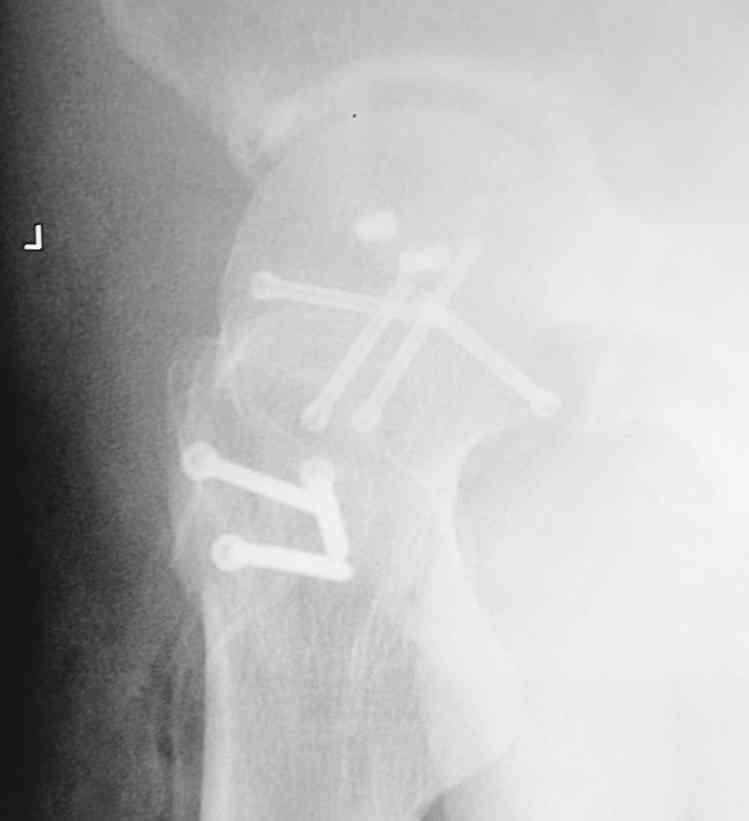

Мужчина, 50 лет, активный, падение с высоты. При поступлении вправление вывиха, других повреждений нет Без значимой сопутствующей патологии, не курит. Стоило ли выполнять остеосинтез при таком оскольчатом переломе или сразу пойти на ТНА?

На снимке №2 есть перелом заднего края суставной впадины,его, я так понял, решили не фиксировать? Фрагмент не очень большой.